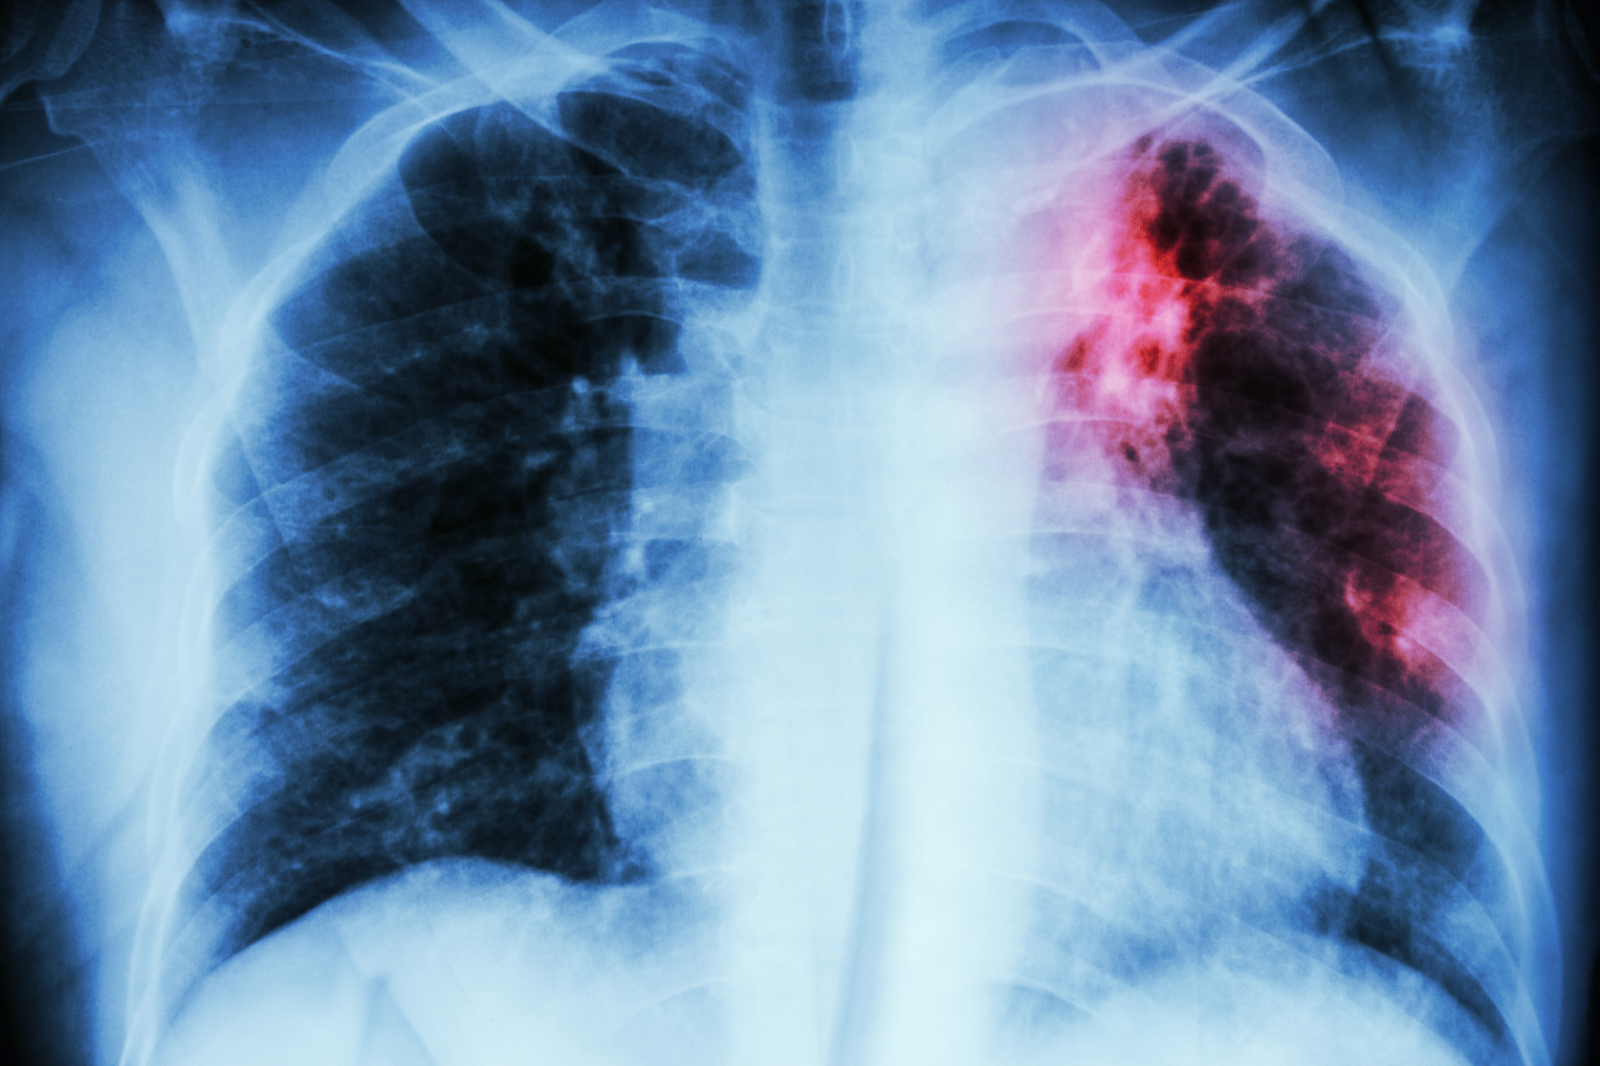

تصویر: ۱۰٪ از کودکان در محیطهای با بار بالای سل ممکن است تا سن ۱۰ سالگی به این بیماری مبتلا شوند. یافتههای جدید همچنین نشان میدهد کودکانی که در محیطهایی با بار بالای سل زندگی میکنند، در طول دوران کودکی، سالانه در معرض خطر بالای ابتلا به عفونت سل هستند. به نقل از bu.edu